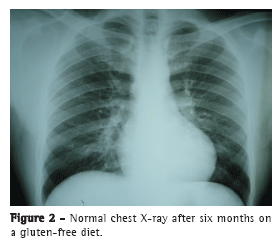

Within six months after the patient was started on a gluten-free diet, there was resolution of the pulmonary lesions and clinical improvement. At this writing, the patient was under follow-up in the department of pulmonology and was asymptomatic, chest X-ray findings and hemoglobin levels being normal (Figure 2).